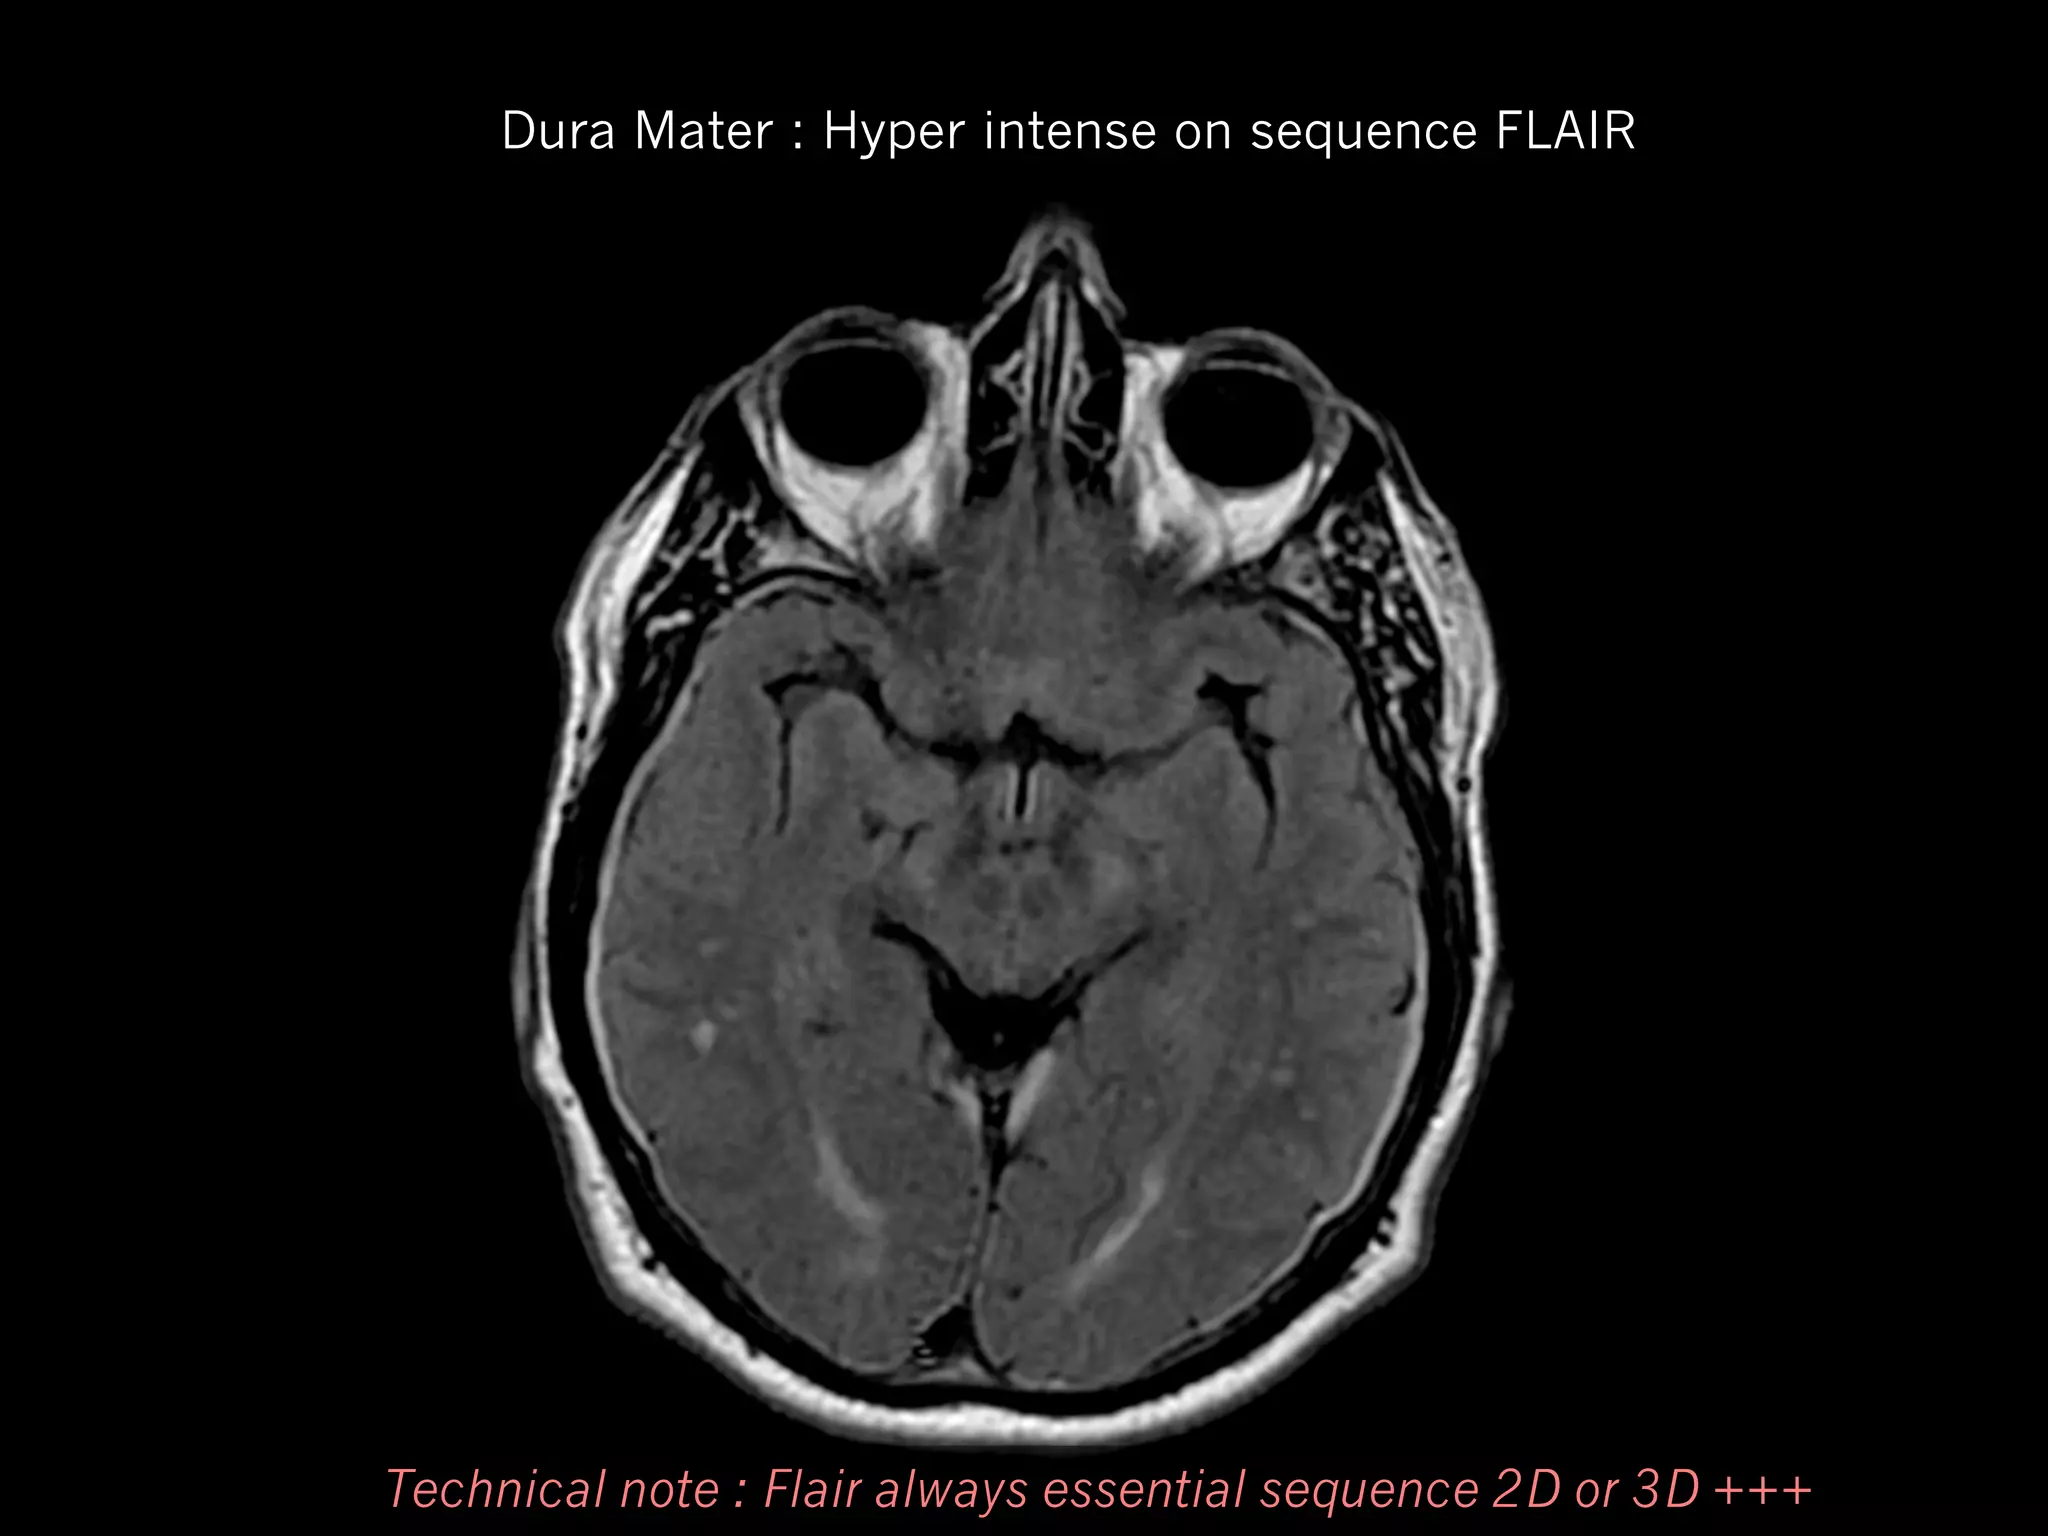

Dura Mater : Hyper intense on sequence FLAIR

Technical note : Flair always essential sequence 2D or 3D +++

Dura Mater :Hyper intense on sequence FLAIR Technical note : Flair always essential sequence 2D or 3D +++